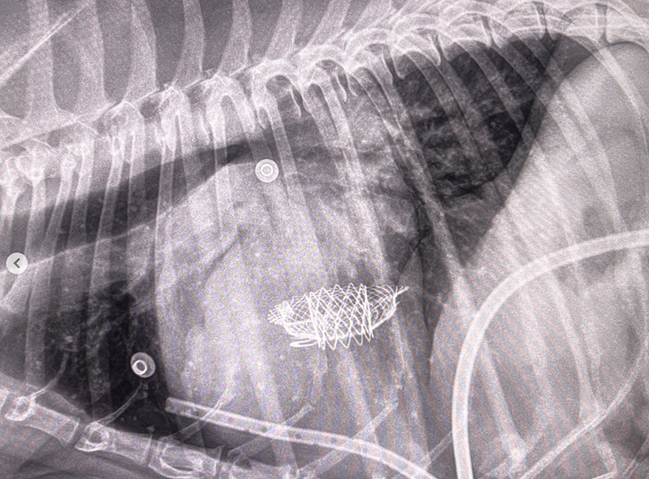

The VHS is not intended to diagnose CHF. It's purpose is to enable veterinarians to more accurately determine enlargement of the heart (called cardiomegaly or dilation) and the progression at which the enlargement is occurring, which usually is due to MVD. However, since MVD normally initially causes only the left atrium (LA) to enlarge, the VHS method is not precise enough to measure only the size of the LA. See for example, the x-ray at left, which shows that the VHS measurements entirely miss the bulbous enlarged LA in the upper right corner of the heart. (Image from Hezzell, 2018.)